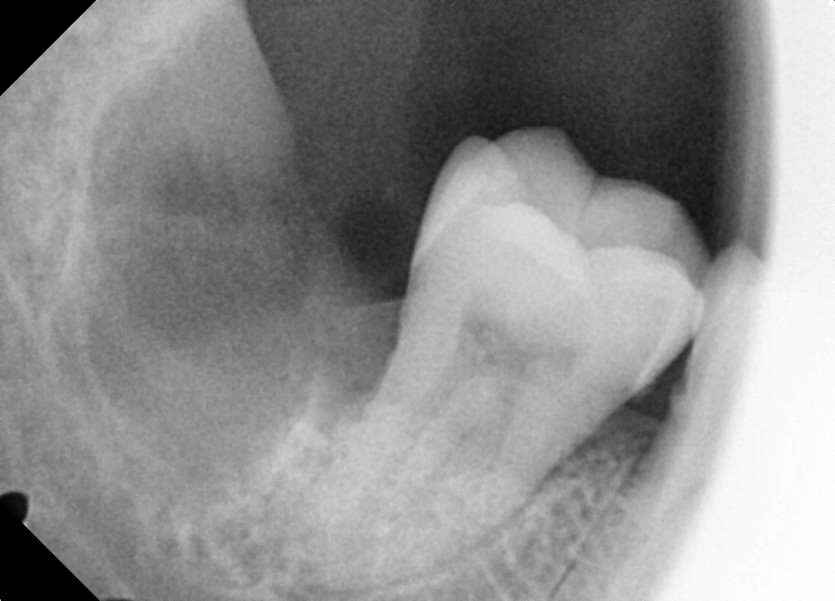

#48 사랑니 발치

구강 외과 전문의가 당일 발치했습니다.